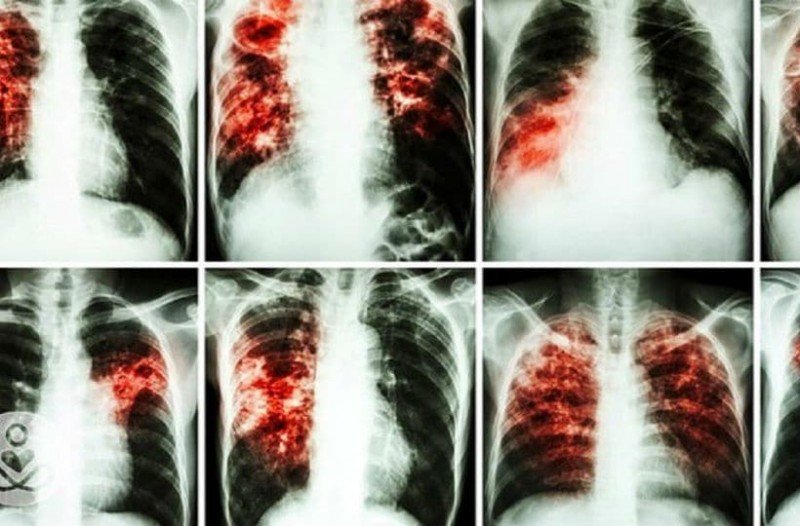

- Καρκίνος